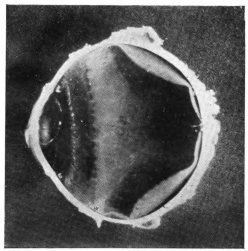

PLATE III.

16.

ABUNDANT EXUDATE INTO VITREOUS CAVITY

curly bracket span

17.

LENS FIRMLY FIXED BY ORGANIZED EXUDATE

18.

LENS FIRMLY FIXED BY ORGANIZED EXUDATE, BUT IN UNUSUAL POSITION

19.

TOTAL DETACHMENT OF RETINA, WITH CYST FORMATION

20.

RECLINED LENS LYING IN FRONT OF THE HYALOID BODY

21.

RECLINED LENS LYING IN FRONT OF THE HYALOID BODYxii